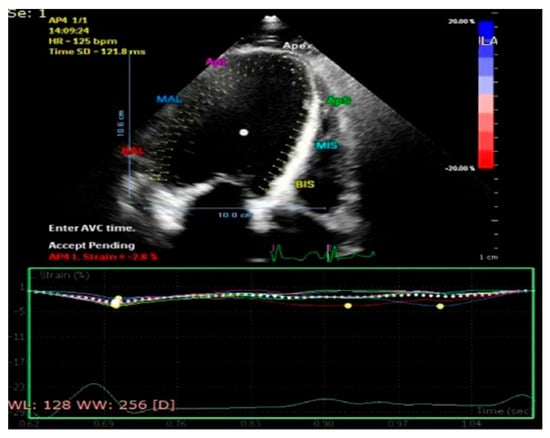

Some echocardiographic aspects revealed in the transthoracic echocardiographic examination before and after CRT are presented in Figure 3, Figure 4, Figure 5, Figure 6, Figure 7, Figure 8 and Figure 9.

Figure 3.

Assessment of myocardial strain from the apical four-chamber view, before therapy with a cardiac resynchronization device.